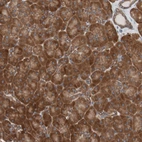

Immunohistochemical staining of human Prostate shows strong cytoplasmic positivity in glandular cells.